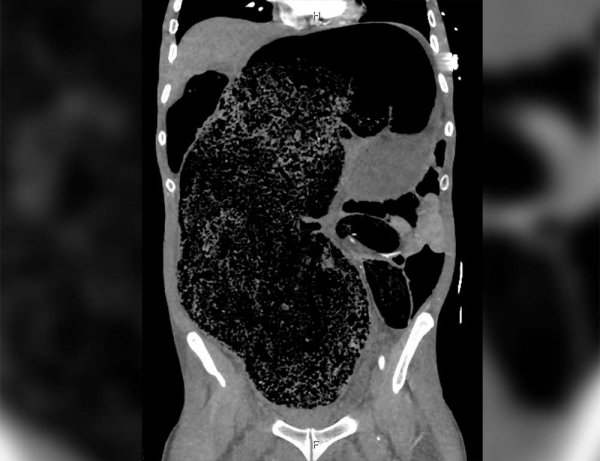

Специалисты обнаружили у мужчины синдром интраабдоминальной гипертензии — это значит, что давление в его животе было слишком высоким. Также у него были признаки почечной недостаточности и метаболического ацидоза — накопления кислот в организме.

Медики установили, что причиной этого состояния стало «массивное фекальное уплотнение неизвестной этиологии». Из-за него давление в брюшной полости поднялось, а также произошла окклюзия правой общей подвздошной артерии — ее проходимость нарушилась.

Мужчину прооперировали, чтобы удалить из кишечника лишнее вещество и снизить давление в брюшной полости. «Значительная фекальная дизимпакция была проведена вручную под общей анестезией, было удалено около двух литров кала», говорится в отчете медиков.